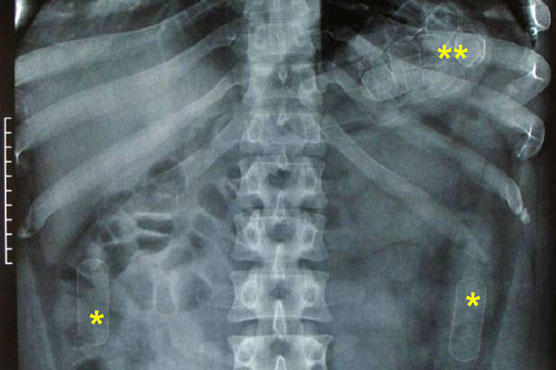

All four were taken to a local hospital, where X-rays revealed they had 54 latex capsules of heroin and 37 of cocaine in their stomachs, 24 of which were in the teenager.

"A total of 2,077 grams of heroin and 1,227 of cocaine hydrochloride, worth up to $100,000 in Central America" were seized, the statement said.